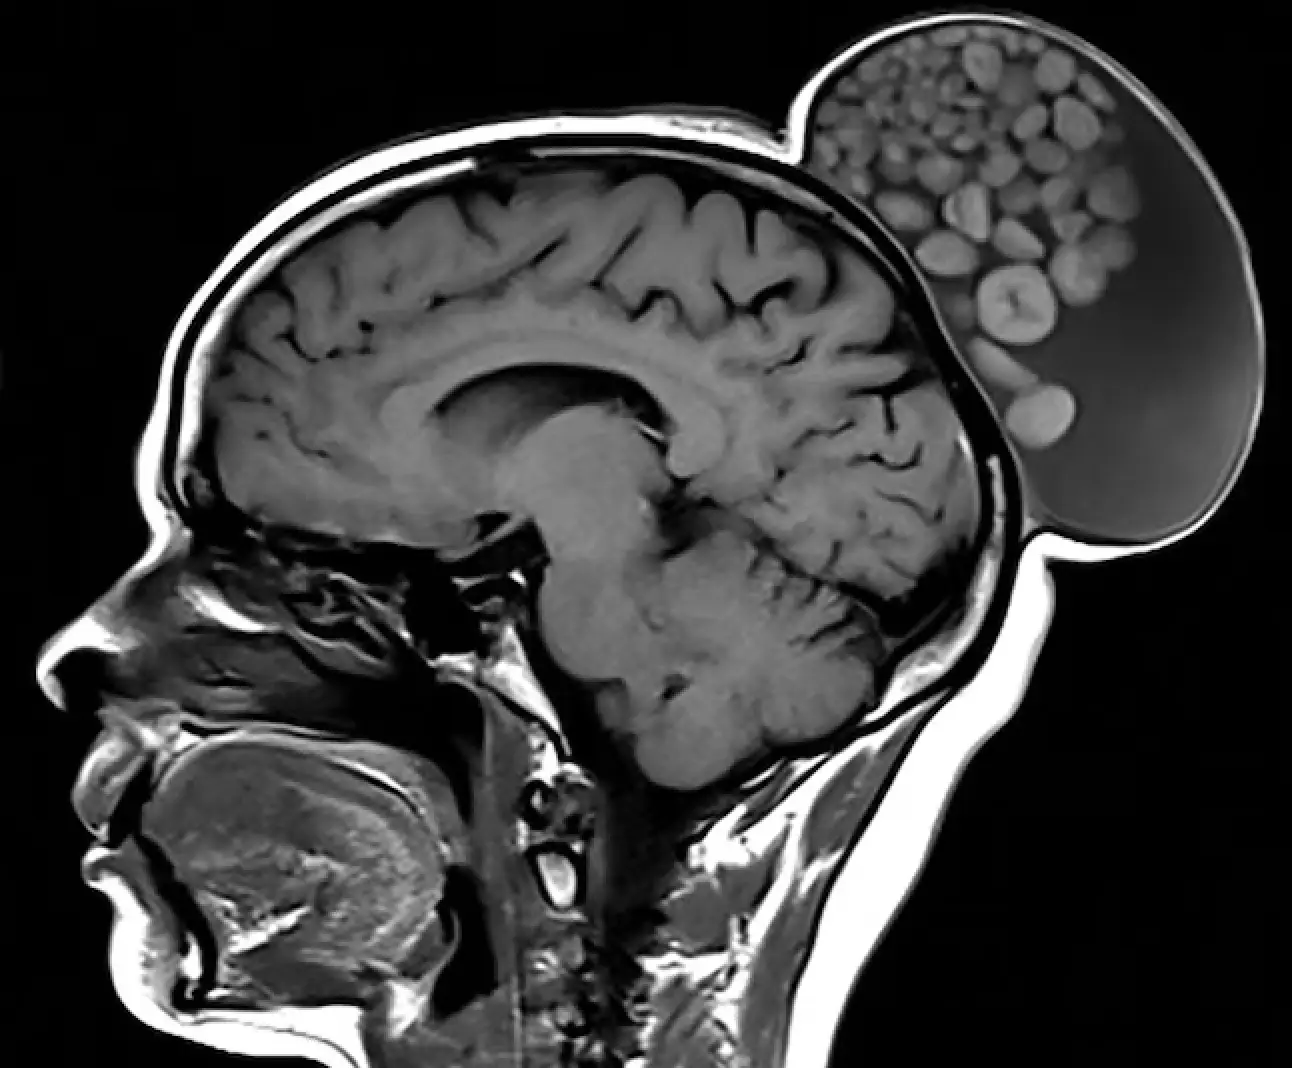

When she arrived at the Sri Sathya Sai Institute of Higher Medical Sciences the tumor measured just shy of six inches in length, around four inches in width and almost five inches in height.

Upon further inspection they discovered dozens of balls of keratin, which looked like marbles, inside the growth - which was hidden at the back of her scalp behind her hair.

At first glance it could have been mistaken for a hair bun.

"The 'marbles' are spherical aggregates of keratin, fat, sebaceous material, fibrin, and hair floating within the fluid matrix of the cyst.

"Though uncommon, the 'sack of marbles' sign is considered pathognomonic of mature cystic teratomas in the head and neck."